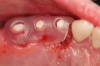

Fig 23. 12 weeks postoperatively.

Figure 23

Figure 23 showed an example of gingival soft tissue creeping occlusally and over the lingual gingival margin of the one-piece ceramic dental implant. This supragingival migration was caused by the exceptional biocompatibility due to the acid-etched surface of the implant, a one-piece implant that prevents bacterial colonization that one may find with two-piece metal-implant systems.